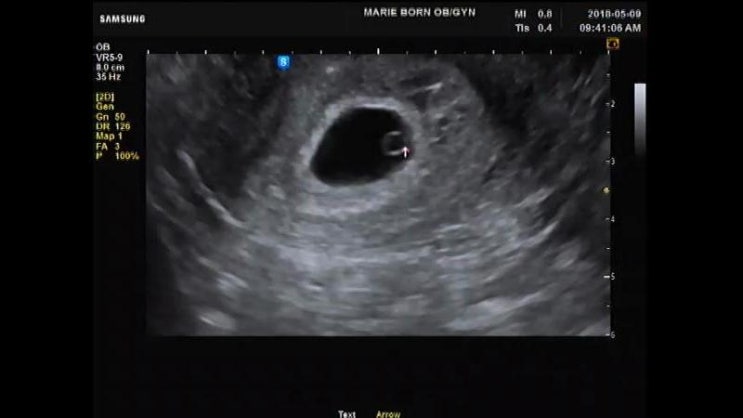

[⚝별하이야기/임신4주-5주]별하의 존재를 처음 알게 된 날!!

얼마만에 새로운 폴더에 글을 올리는지 모르겠어요~~~ 별하의 존재를 알게 된 지 벌써 100일하고 4일...